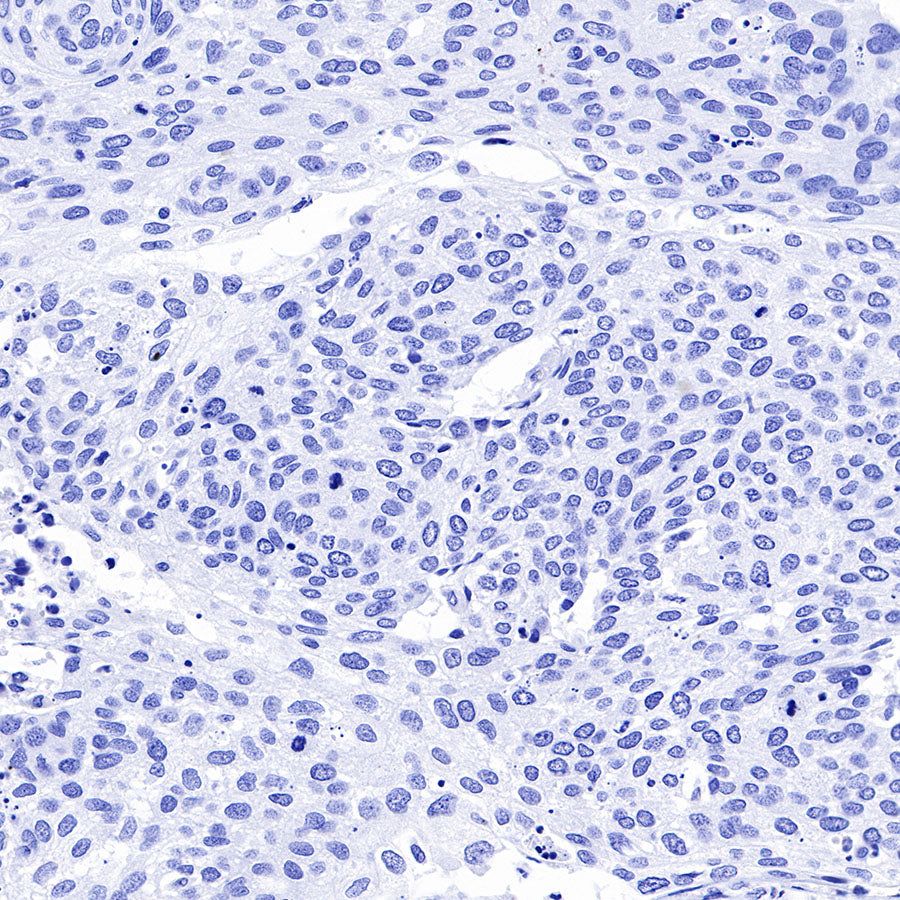

Negative control: IHC shows negative staining in paraffin-embedded human cervical squamous cell carcinoma. Anti-GPA33 antibody was used at 1/2000 dilution, followed by a HRP Polymer for Mouse & Rabbit IgG (ready to use). Counterstained with hematoxylin. Heat mediated antigen retrieval with Tris/EDTA buffer pH9.0 was performed before commencing with IHC staining protocol.